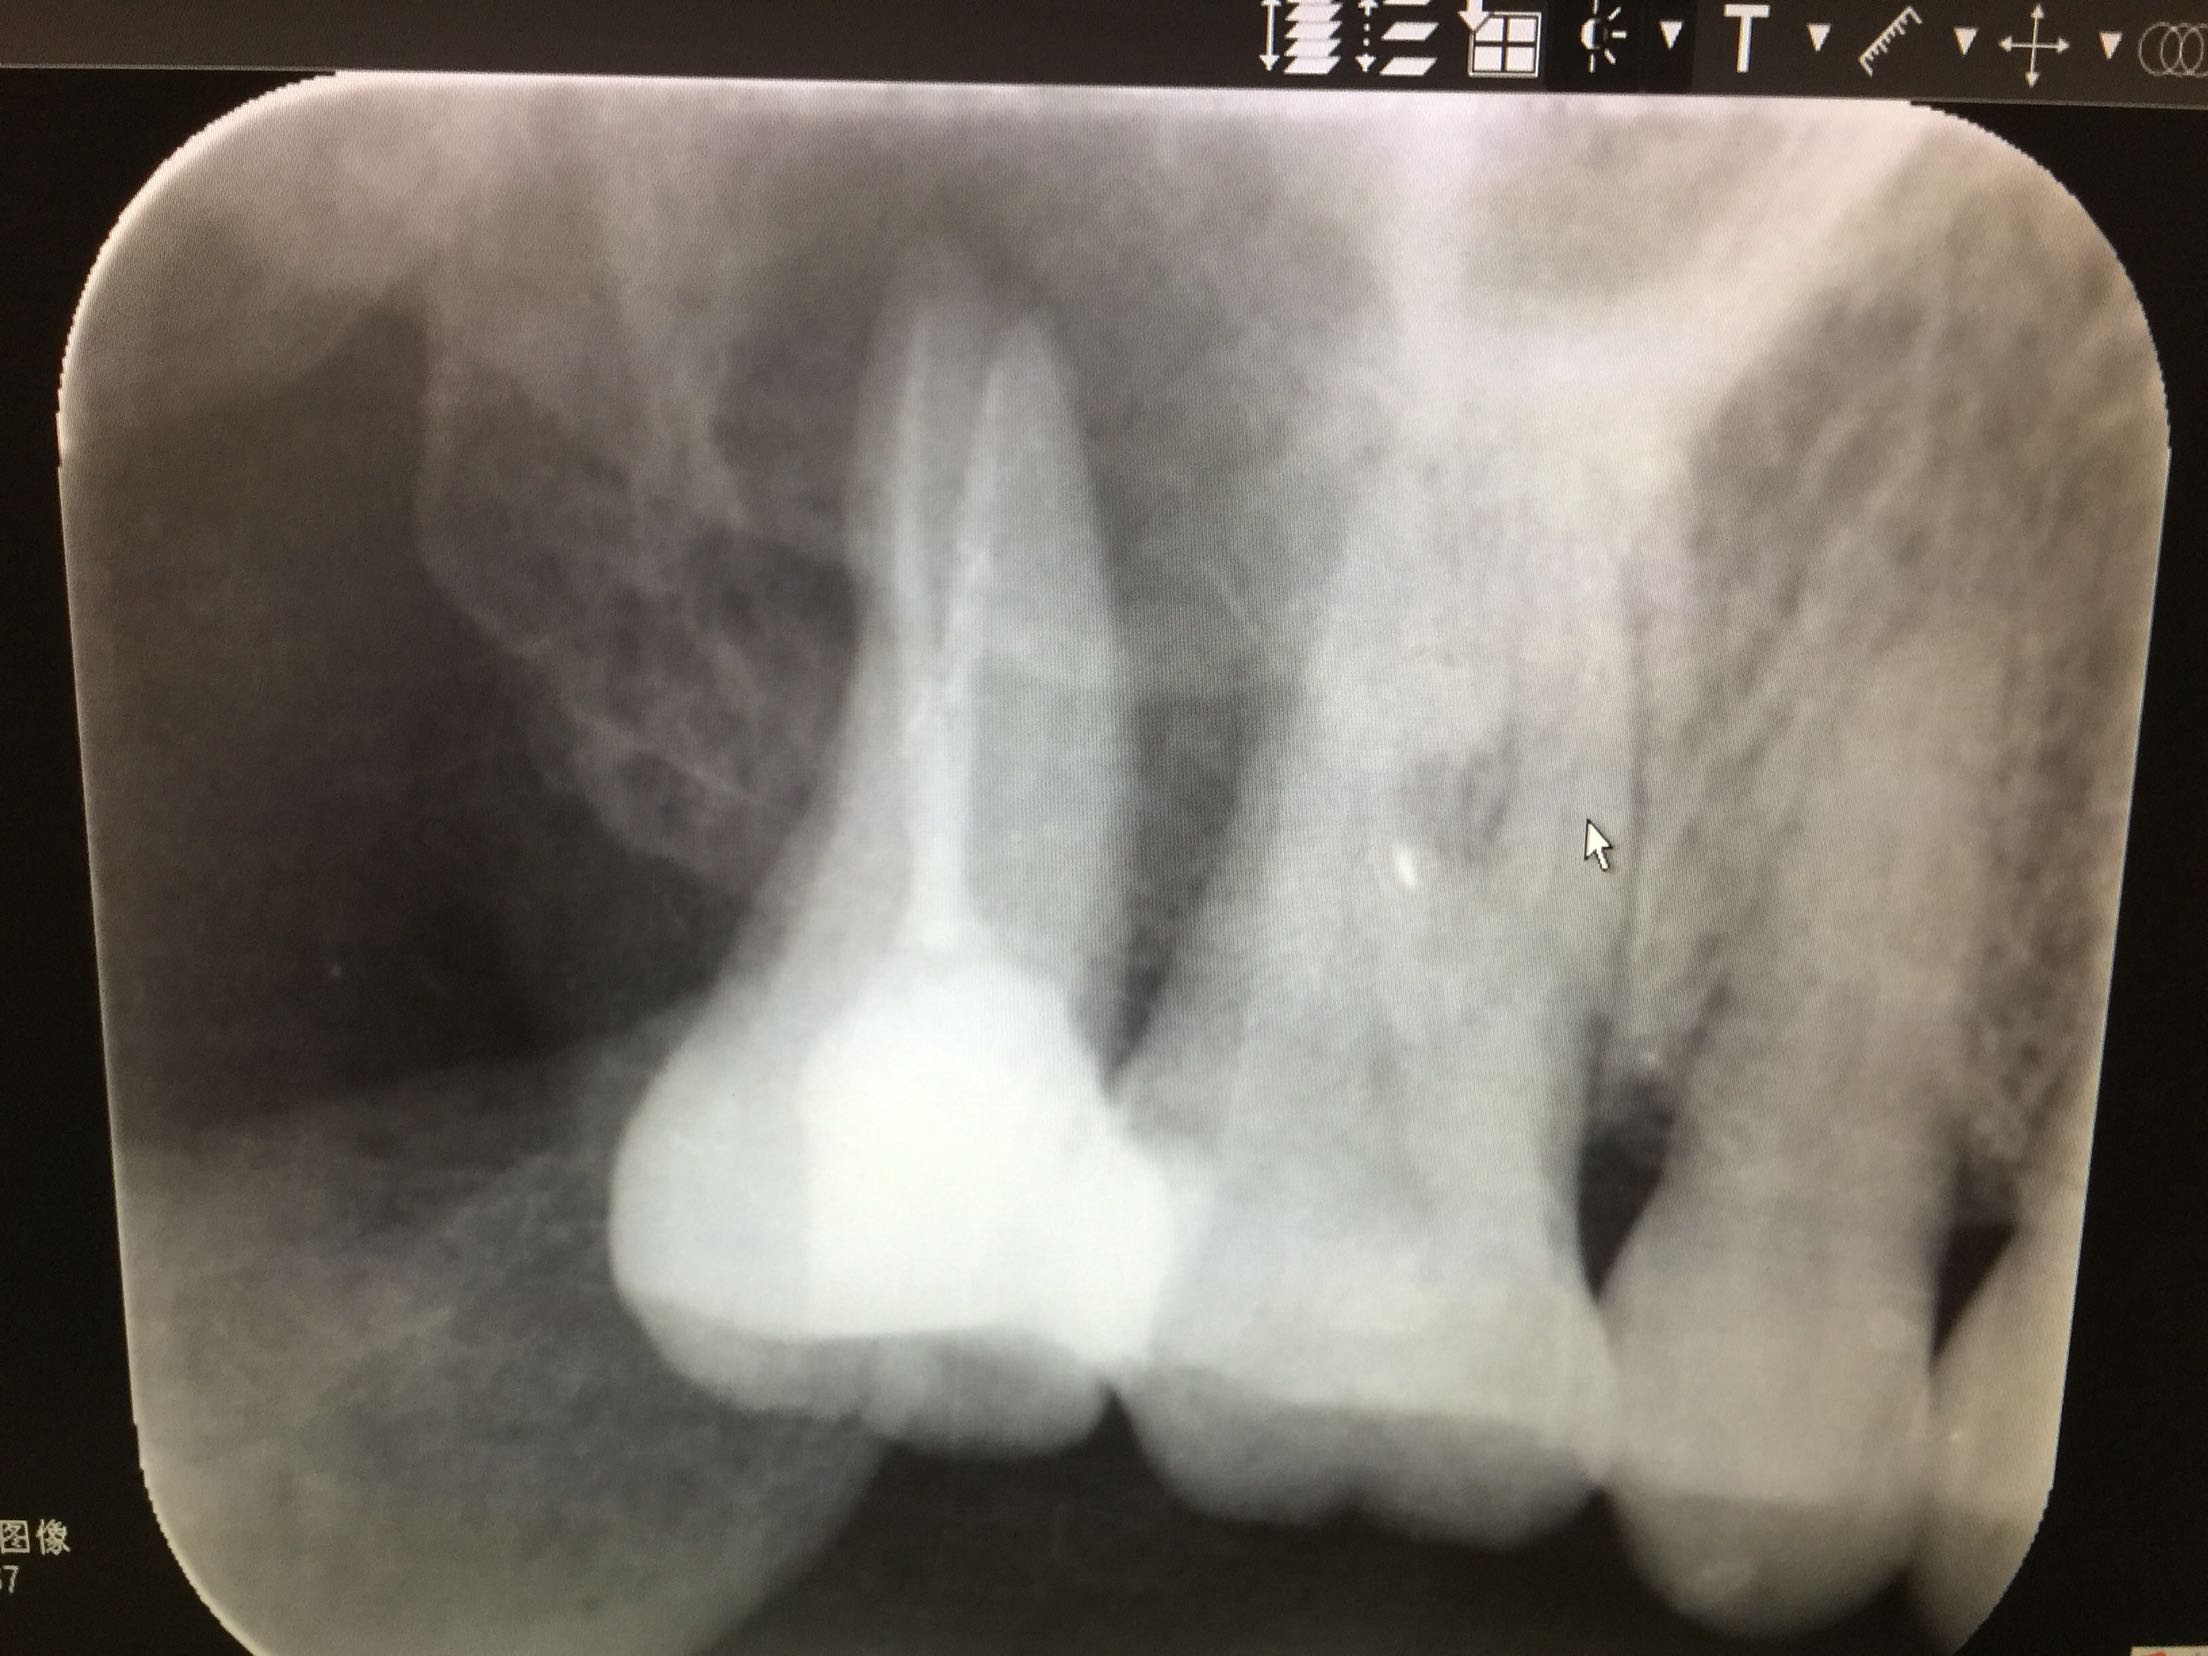

检查 17牙合面可见树脂补物,无继发龋。冷-,探-,叩++,不松。全口卫生差,全口牙龈不同程度退缩。 X线示:17牙已行根管治疗,根充不完善,很尖有暗影。

诊断:17牙根尖周炎 治疗计划:全口龈上龈下洁治术 17牙试行根管再治疗+冠保护 治疗. 17牙去除原补料,探查根管口,双根管,用氯仿溶解原牙胶,清扩,消毒,内封进口氢氧化钙,一周后复诊。 复诊. 诊间患牙疼痛消失,检查 冷-,探-,叩+-,不松。暂封完好,去除暂封,试主尖,合适,热充,回填。患者要求暂不行冠修复。已向患者交待不做冠保护可能会导致牙齿折裂等情况,患者知情同意。